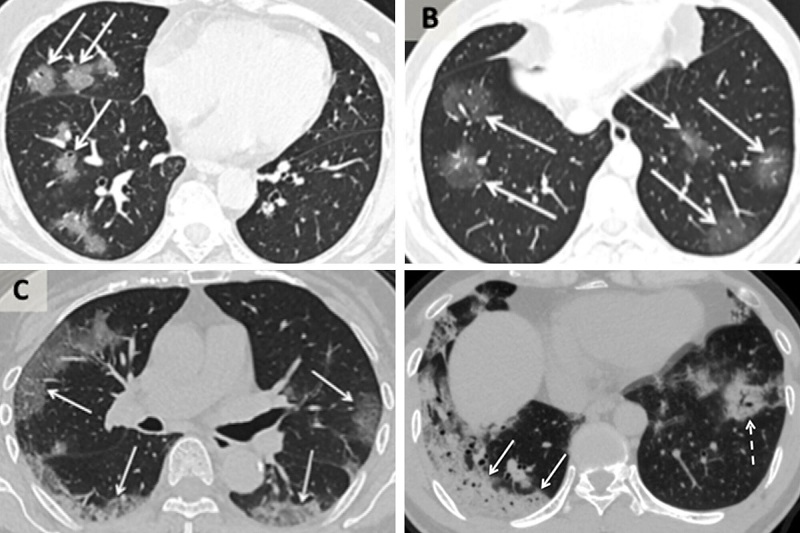

Далее, по словам доктора Шу-Юань Сяо, вирус начинается в периферических областях с обеих сторон легкого и двигается к верхним дыхательным путям и трахее.

На компьютерной томографии в легком зараженного человека видно туманную завесу, которую легко спутать с другими респираторными заболеваниями.